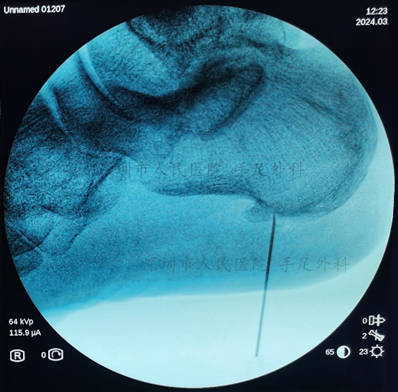

图6:术中跟骨骨刺定位

图7:术中证实跟骨骨刺已清除